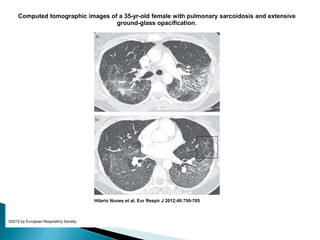

Computed tomographic images of a 35-yr-old female with pulmonary sarcoidosis and extensive

ground-glass opacification.

Hilario Nunes et al. Eur Respir J 2012;40:750-765

©2012 by European Respiratory Society